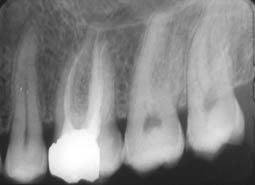

Lorsque le stop indiquant la longueur de travail, arrive au contact du repère anatomique choisi sur la couronne clinique, la descente est interrompue. Un cliché radiographique de contrôle est réalisé (5).

- obturation tridimensionnelle (7,8) des volumes préparés ou débridés (Fig.3),

- respect et adaptation aux canaux étroits, aux coudures, aux courbures canalaires (fig.4),canaux accessoires et ramifications,

- contrôle excellent de la longueur d’obturation( 9,10) ;